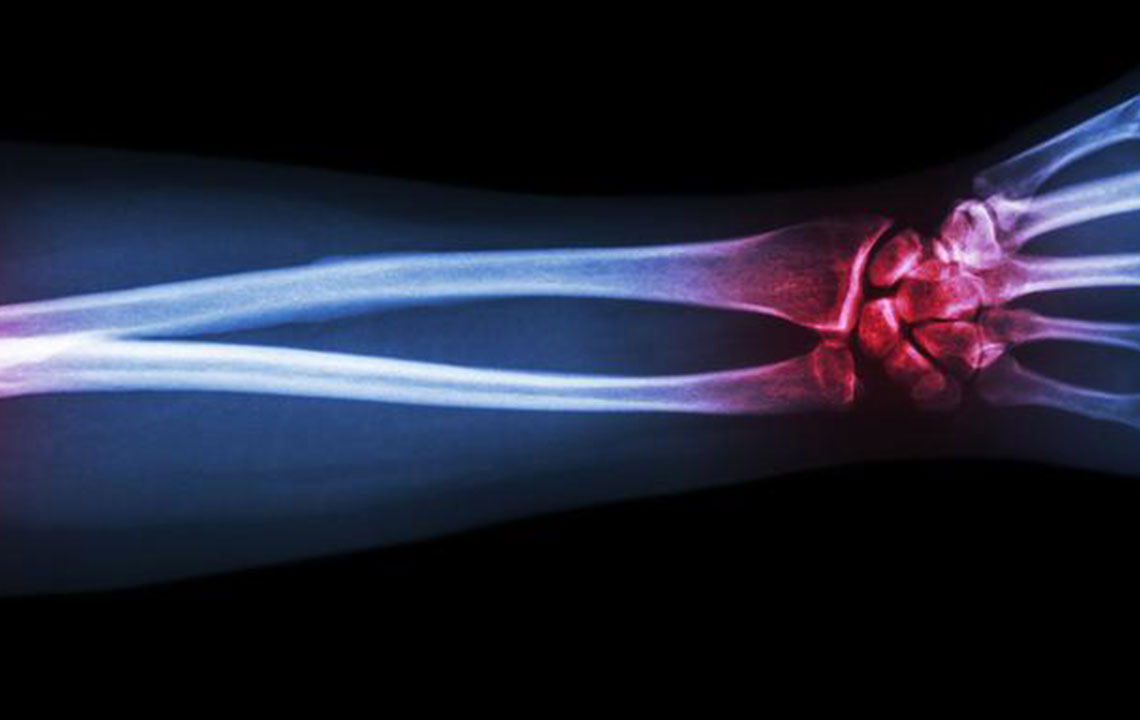

Gout is a type of arthritis that primarily attacks the joints and other body parts like the ears, wrists, knuckles, knee, ankles, and other small joints. It is often characterized by painful swelling, stiffness, and inflammation of these affected joints. The swelling and stiffness are mainly the results of excess levels of uric acid forming crystals in the joints. The pain is due to the inflammatory response to the crystals formed.

The deposition of uric acid crystals in the joint causes inflammation and makes the movement of the joint agonizing. The elevated levels of uric acid in the system also causes the depositing of crystals in the kidney, which, in turn, leads to stone formation.